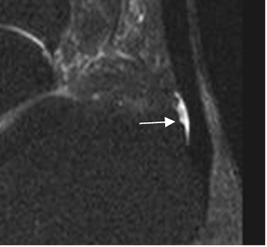

Fig 79. Peritendinosis del aquiles.

RM sagital en STIR: Tendón normal, con líquido en la bursa pre-aquiliana.